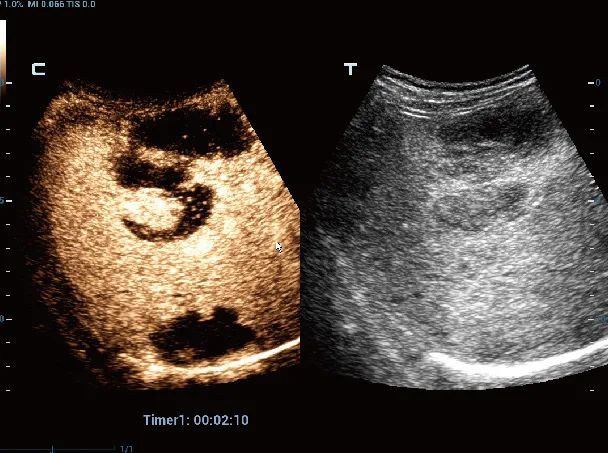

肝癌造影